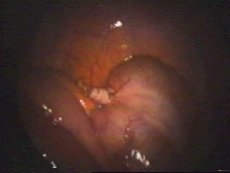

Colocado la pieza dentro de una bolsa de Endocatch para ser extraído por el ombligo